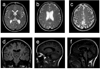

Recessive mutations in GJC2, the gene-encoding connexin 47 (Cx47), cause Pelizaeus-Merzbacher-like disease type 1, a severe dysmyelinating disorder. One recessive mutation (p.Ile33Met) has been associated with a much milder phenotype--hereditary spastic paraplegia type 44. Here, we present evidence that a novel Arg98Leu mutation causes an even milder phenotype--a subclinical leukodystrophy. The Arg98Leu mutant forms gap junction plaques in HeLa cells comparable to wild-type Cx47, but electrical coupling was 20-fold lower in cell pairs expressing Arg98Leu than for cell pairs expressing wild-type Cx47. On the other hand, coupling between Cx47Arg98Leu and Cx43WT expressing cells did not show such reductions. Single channel conductance and normalized steady-state junctional conductance-junctional voltage (G(j)-V(j)) relations differed only slightly from those for wild-type Cx47. Our data suggest that the minimal phenotype in this patient results from a reduced efficiency of opening of Cx47 channels between oligodendrocyte and oligodendrocyte with preserved coupling between oligodendrocyte and astrocyte, and support a partial loss of function model for the mild Cx47 associated disease phenotypes.